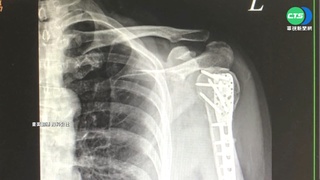

氣象站說受東北季風影響,當天有發布強風特報,15:00花蓮市,測得7級陣風,每秒風速來到15.7M,確實對騎車會造成影響,七級陣風,樹會全身搖動逆風行走困難,更何況是在橋面上,風速又更大,當時騎士上橋後,剛好有一陣強風,導致機車失去平衡撞擊護欄,婦人直接彈飛,掉落到橋下平面道路,花蓮分局豐川所長林庭安說:「腿部受傷經送醫救治後無大礙,然後距離地面大概兩層樓的高度。」

警方說腿部受傷橋距離地面兩層樓高度,一場陣風,害得人自撞骨折,幸好沒有生命危險,但影片曝光也讓民眾驚呼,風大騎車還是得注意安全。